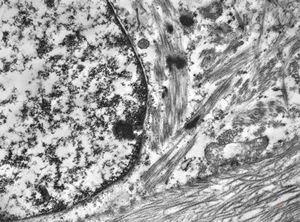

F,32y. | transversally sectioned skeletal muscle cell

mouse skeletal muscle cell - transversal section